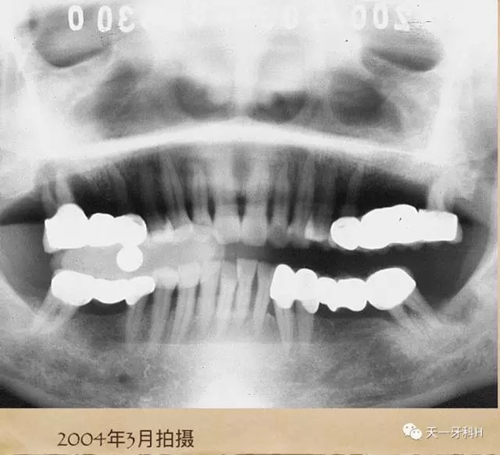

該患者2004年3月16日來本診所就醫(yī),這張曲面斷層片就是當時拍的,患者之前在外院后牙區(qū)全部做了烤瓷連橋,從這張曲面斷層片上看:右上七牙槽骨已經破壞到了根尖,右上五也出現(xiàn)了牙周膜間隙增寬,左上后牙的烤瓷橋的基牙也開始出現(xiàn)問題了,我常常講:牙周病患者盡量不要做烤瓷牙,很多患者不理解,我用事實說話:這個牙周病患者就是一個烤瓷牙的受害者,四個后牙區(qū)全部做了烤瓷橋!17已經牙槽骨破壞到達了根尖區(qū),15、25、28已經開始了牙槽骨破壞,我當時勸她拆除烤瓷橋,她不聽我的話,我只好拍片記錄下來她的現(xiàn)狀,下面就是她當時的牙片: